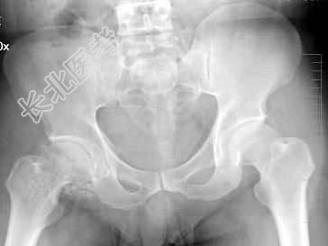

- 单项选择题男,38岁, 右髋关节疼痛不适1年余,跛行, 骨盆正位片如图所示,最可能的诊断是 ( )

A、右髋关节退行性骨关节病

B、右髋关节滑膜骨软骨瘤病

C、右髋关节骨化性肌炎

D、以上均不正确

E、以上均正确